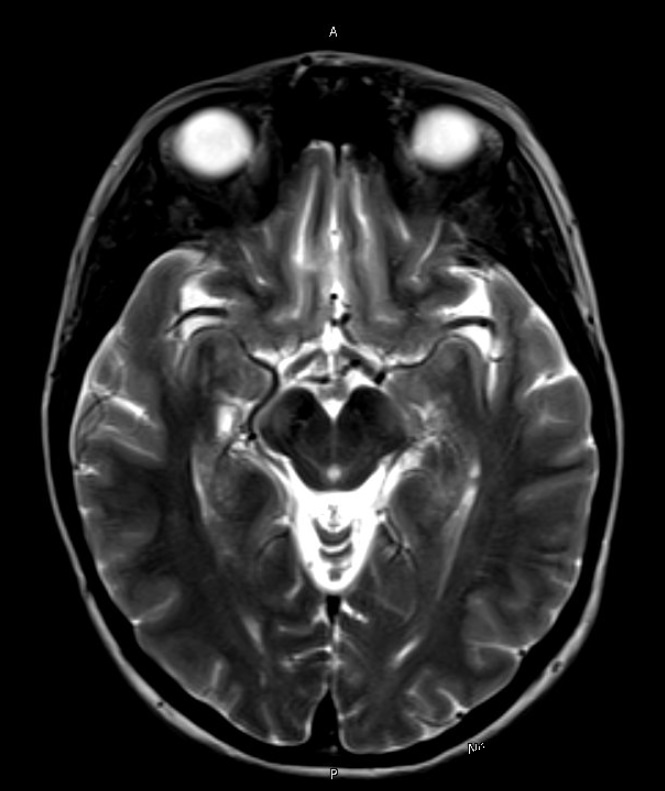

Results: Genetic testing of 61 genes revealed two heterozygous mutations of uncertain significance (c.2233C>T p.His745Tyr and c.8341T>A p.Ser2781Thr) in the VPS13A gene. Magnetic Resonance Imaging (MRI), with absence of the “swallow tail” sign in the left cerebral peduncle. PET-F-Dopa, uptake consistent with presynaptic alteration of the nigrostriatal system and the LD test showed an improvement of >83% within 1 hour after taking medication.

Image 1. A (MRI 06.11.23)